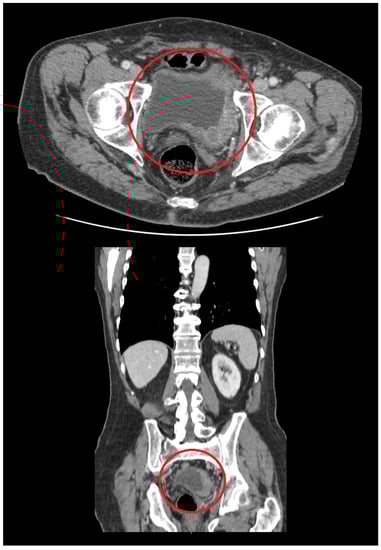

3. Primary DLBCL of the Urinary Bladder: Clinical Features

4. Diagnostic Approach for Primary Urinary Bladder Lymphoma